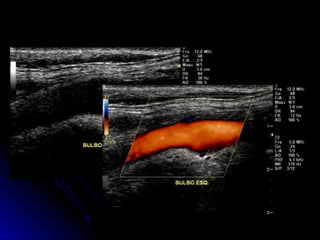

DocumentaçãoDocumentação

ACC, Bifurcação e BulboACC, Bifurcação e Bulbo

Modo B e ColorModo B e Color

ACC, ACI e ACEACC, ACI e ACE

Espectral com VPS e VDEspectral com VPS e VD

Documentar a correção do ângulo DopplerDocumentar a correção do ângulo Doppler